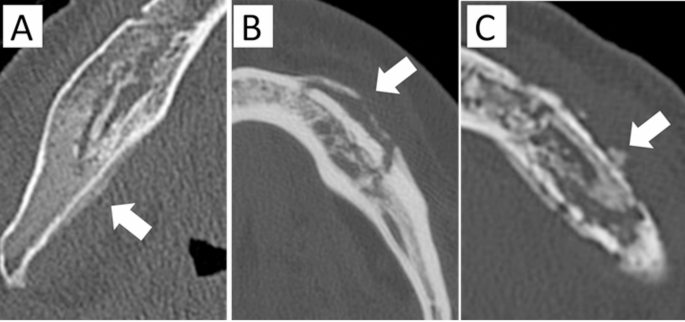

Classified by the presence and morphology of periosteal new bone formation:

(−): No periosteal reaction.

Attached type—new bone is formed parallel to the mandible, without a gap.

Gap type—new bone is formed parallel to the mandible, separated by a gap.

Irregular type—new bone is formed with an irregular shape.